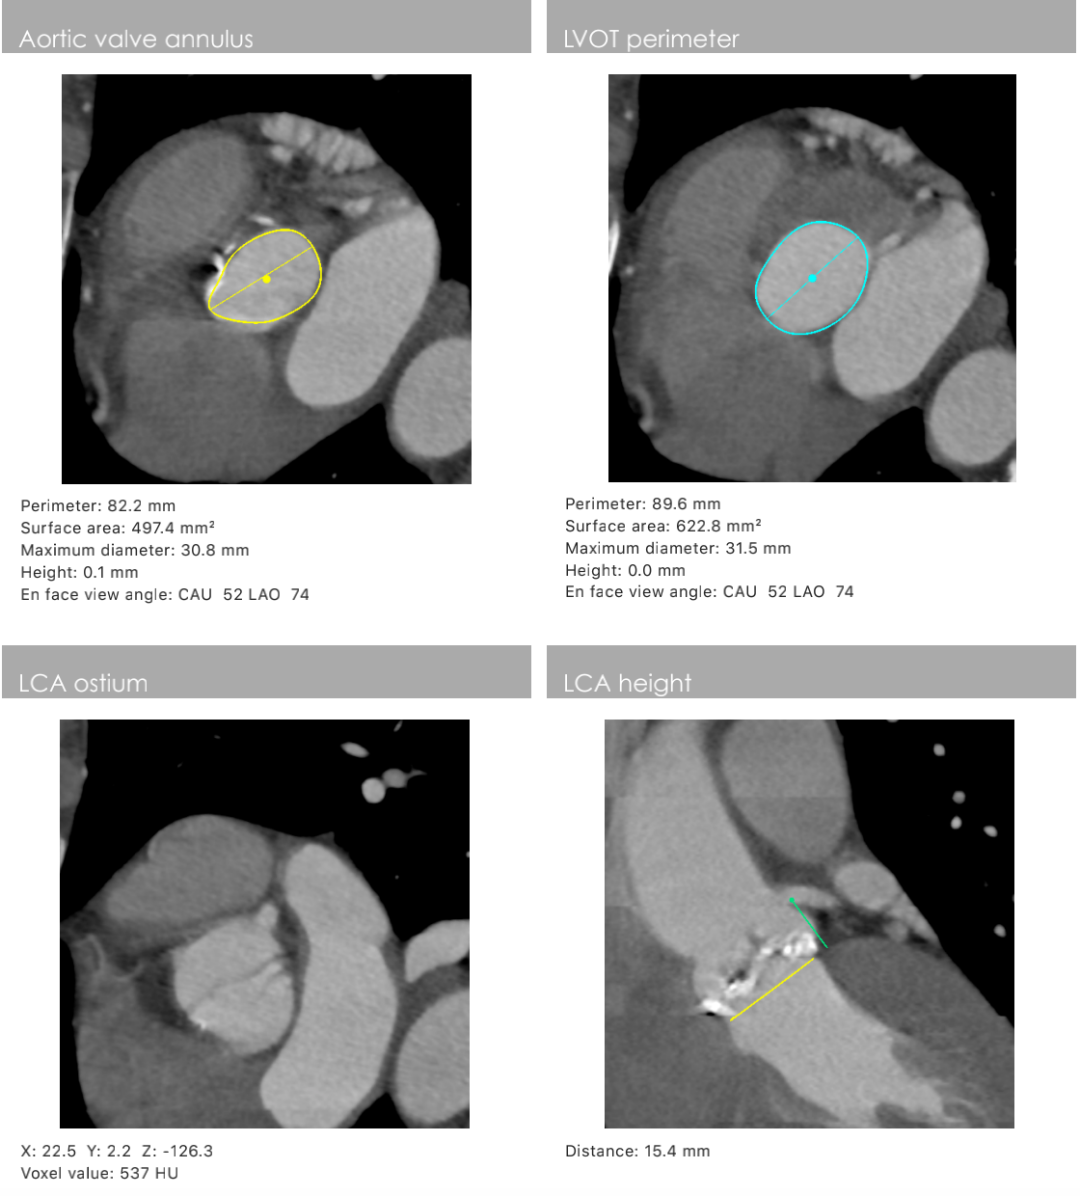

主动脉瓣环周长82.2mm(平均直径26.1mm),流出道周长89.6mm(平均直径28.5mm),左冠高度:15.4mm,右边冠高:14.9mm,主动脉窦宽28.7mm/33.7mm/34.9mm、STJ周长:93.5mm(平均直径29.7mm)高度22.2mm,升主动脉周长:111.7mm(平均直径35.5mm)。

术前心胸外科、心血管内科、超声科、麻醉科、体外循环、介入室等科室进行了术前讨论和术前策略分析:该患者主动脉瓣属于钙化狭窄的Type0型二叶瓣,左右冠脉同窦,无冠窦可见团状钙化,左右同窦钙化相对较少,主动脉瓣环周长82.2mm、呈现椭圆形,左室流出道周长89.6mm,主动脉窦宽28.7mm/33.7mm/34.9mm、窦宽可,STJ周长93.5mm、高度22.2mm,升主动脉周长111.7mm。患者心室壁明显增厚心尖较薄。左冠高度15.4mm右冠高度14.9mm,双冠高度可。患者右股动脉分叉点位于股骨头下缘,穿刺点内径为8.1mm,血管无明显钙化轻度迂曲。左股动脉分叉点位于股骨头下缘,穿刺点内径为7.8mm,血管无明显钙化轻度迂曲。选择右侧股动脉为主入路,左侧股动脉可作为辅入路;考虑患者主动脉瓣二叶式畸形,钙化严重,采用DOWNSIZE策略,综合评估选择20mm/22mm球囊预扩;患者瓣环周长82.2mm,考虑TAV27型号瓣膜。